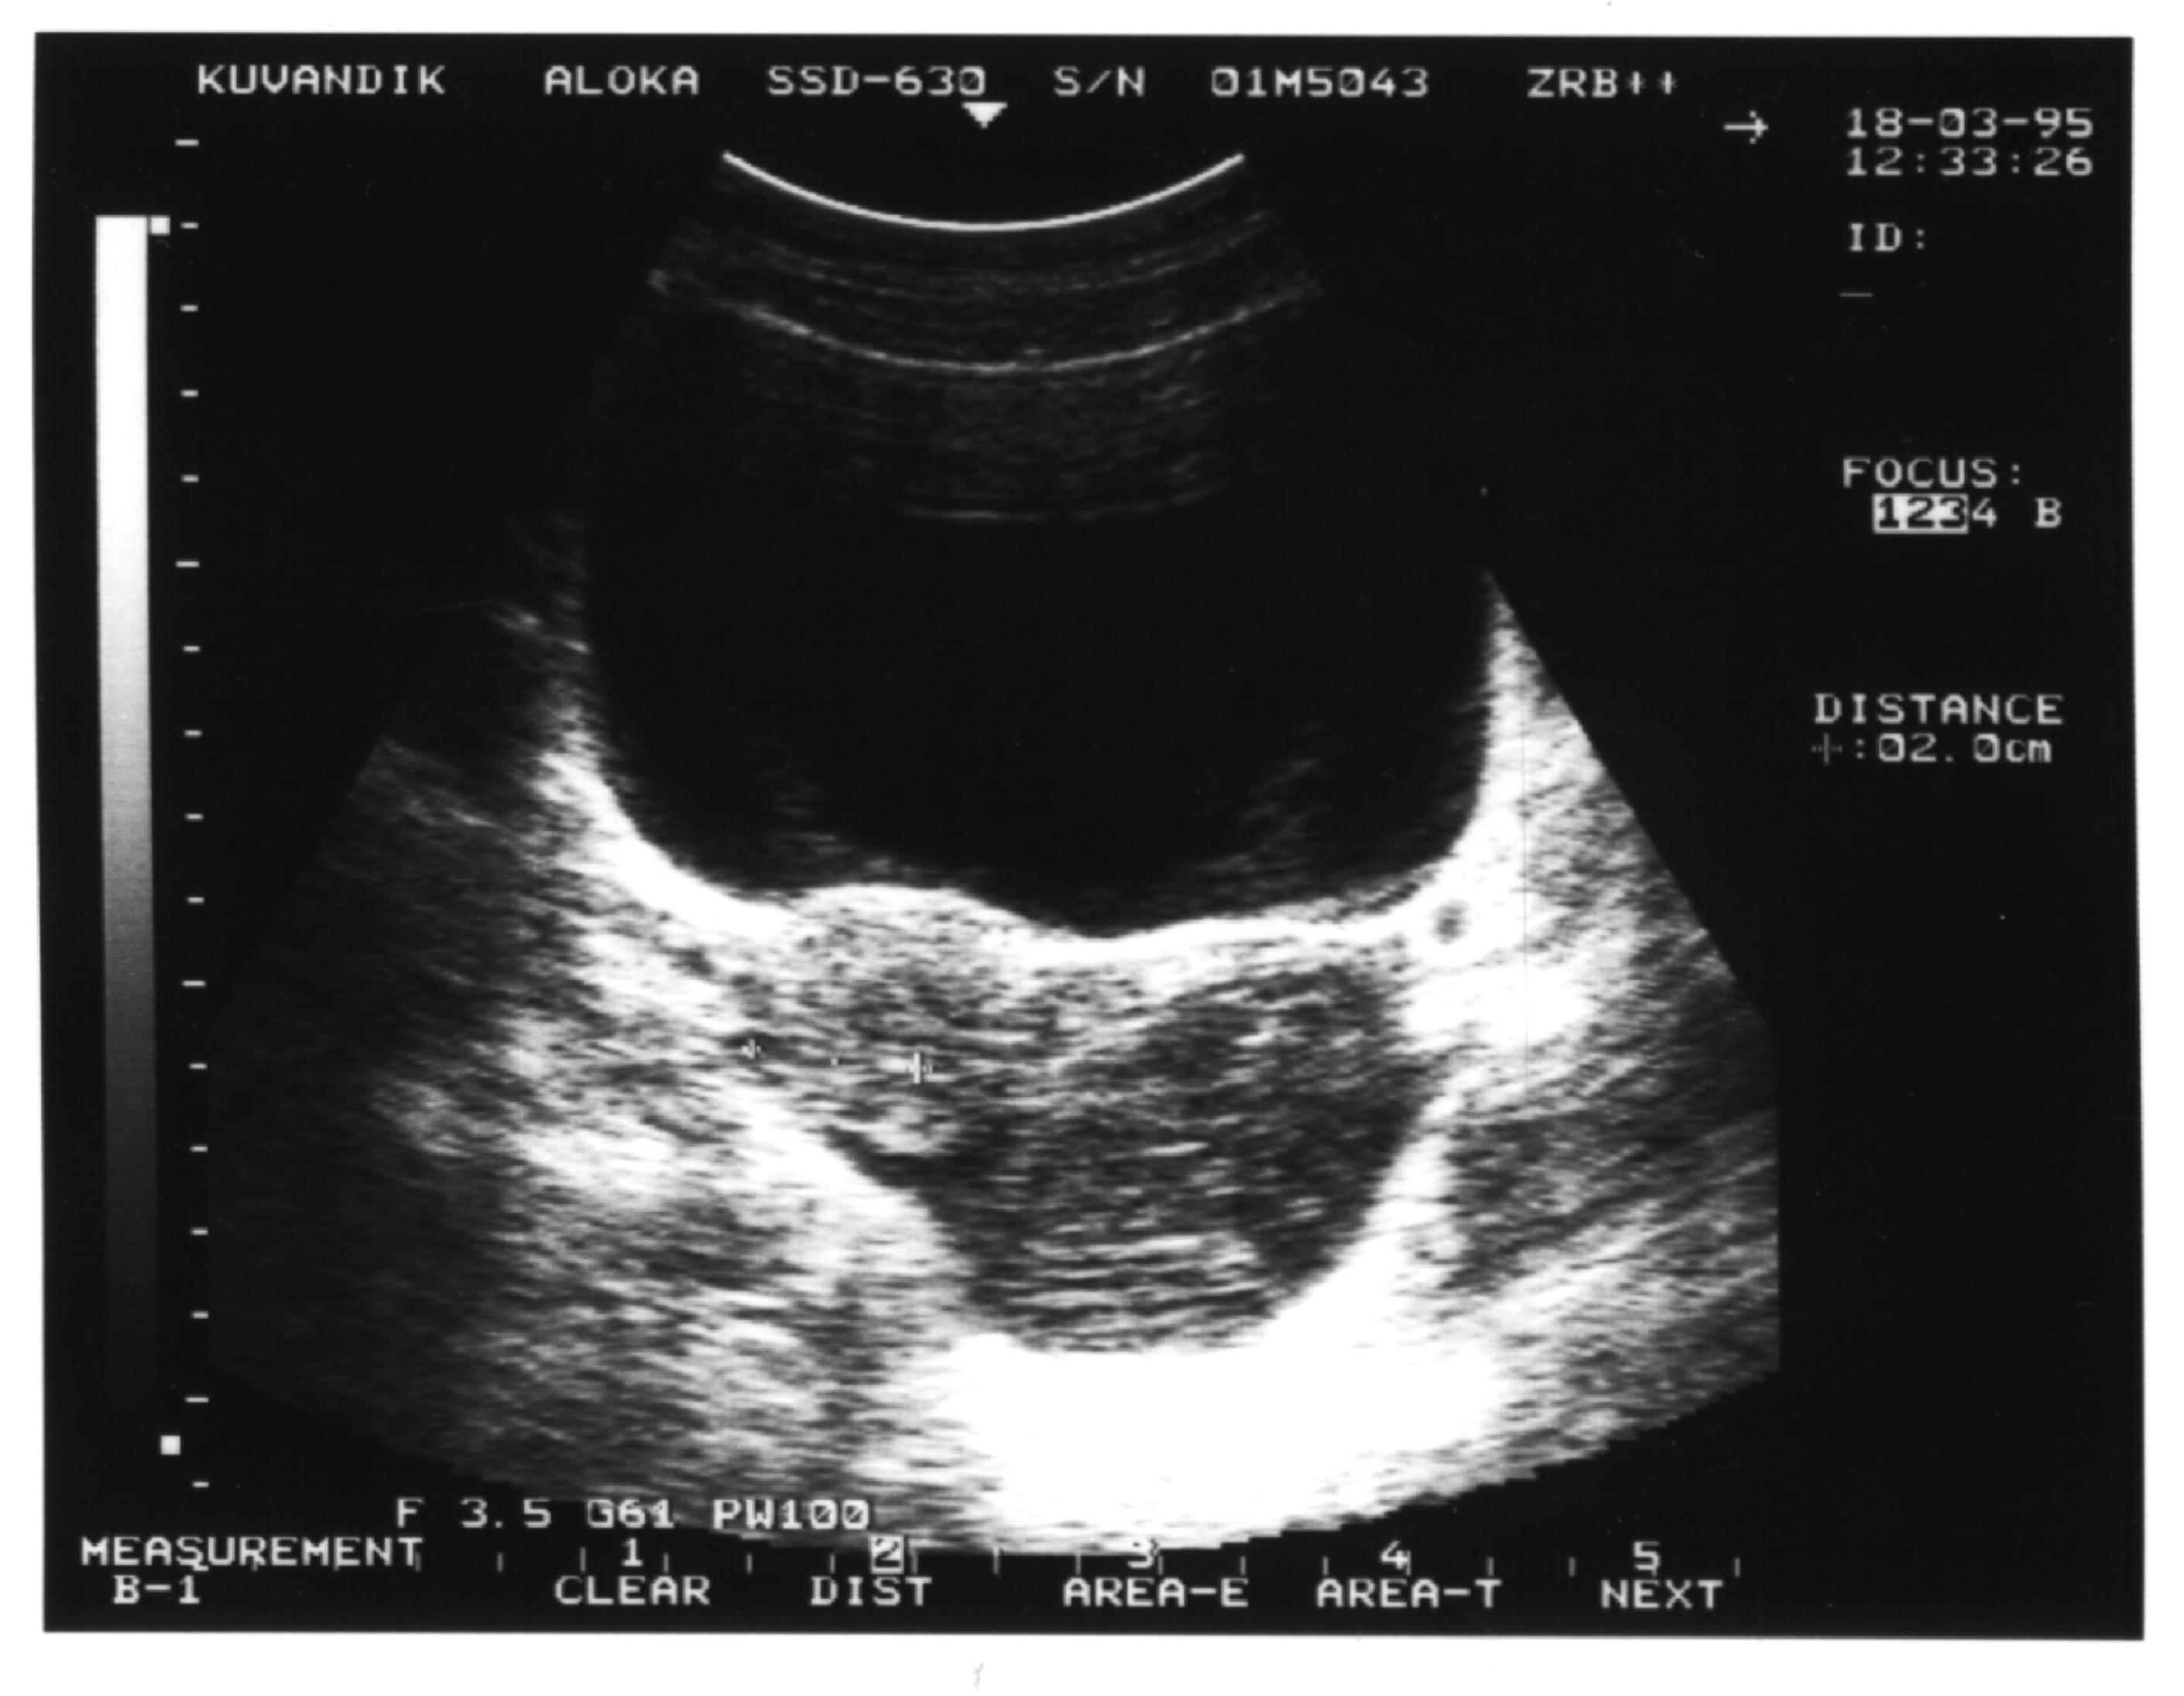

1

Рисунок 1. Однокамерный вариант гидро-сальпингса.

. Однокамерный вариант. В пространстве между од­ним из яичников и маткой (вдоль боковой стенки матки), то есть в одной из параметральных областей, выявляется жидкостное образование правильной вытянутой формы со значительным преобладанием продольного размера над поперечным. При этом конфигурация патологического очага может быть овальной (рис.1), ве­ретенообразной или S-образной. Структура жидкого содержимого однородная. Матка, эндометрий и яичники не изменены. На стороне поражения почти всегда лоцируется неизмененный яичник. Оптимальные условия для визуализации патологического очага со­здаются при поперечном обзорном сканировании с использованием спо­соба дозированной компрессии передней брюшной стенки УЗ-датчиком (желательно секторным).

Как правило, этот вариант воспаления маточных труб встречается у молодых женщин и часто обнаруживается при первичном обращении к гинекологу.